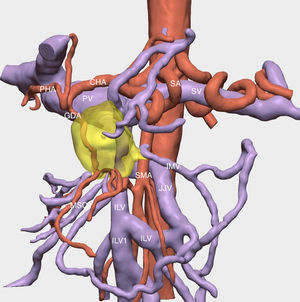

Técnica quirúrgica (vídeo cirugía)El uso de shunt íleo-cava transitorio se indicó en un paciente de 45 años afecto de adenocarcinoma de páncreas localmente avanzado que condicionaba una severa colateralidad venosa, con mutación BRCA2; tras recibir 11 ciclos de neoadyuvancia con esquema FOLFIRINOX, con buena tolerancia. Finalizado este, se realizó estudio mediante tomografía computarizada (TC) toraco-abdominal, PET/TC, y resonancia magnética nuclear (RNM), descartando afectación a distancia. Tras presentar el caso en comité multidisciplinario se planificó la intervención con ayuda de estudio 3D13 (figs. 1, 2, 3 y 4)(https://www.cellams.com). En el estudio preoperatorio se evidenció lesión pancreática con afectación del confluente venoso EMP con extensión hasta la confluencia de dos venas ileales (Vil1 y Vil2) y yeyunal (VYy), y contacto con la arteria mesentérica superior (AMS). La afectación de toda la extensión de la vena mesentérica superior (VMS) comportaba la imposibilidad de la anastomosis con seguridad.

Estudio 3D preoperatorio13. Se evidencia la oclusión del eje esplenoportomesentérico y abutment de la arteria mesentérica superior por el tumor.

SMA: arteria mesentérica superior; CHA: arteria hepática común; PHA: arteria hepática propia; GDA: arteria gastroduodenal; SA: arteria esplénica; PV: vena porta; SV: vena esplénica; VIL: vena ileal; VIL1: vena ileal tributaria 1; VIL2: vena ileal tributaria 2; VYY: vena yeyunal; IMV: vena mesentérica inferior; MSC: mesocolon.

En amarillo se señala el tumor pancreático.

Detalle de la vascularización venosa del estudio 3D13.